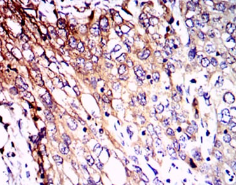

IHC    1/200 - 1/1000